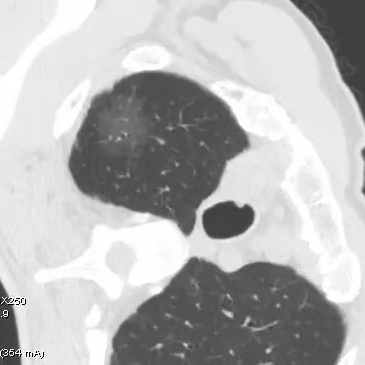

健康直通车: 健康是生命的宝贵财富,也是幸福生活的基石。为了更好地服务广大百姓,传播健康知识,葫芦岛市第二人民医院推出“健康直通车”专题栏目,将专业的医学知识以通俗易懂的方式传递给每一位市民,掌握科学的疾病预防方法,共同构筑健康中国的坚实基石。 什么是肺结节 肺结节是指肺内直径小于或等于3cm的类圆形或不规则形病灶,影像学表现为密度增高的阴影。大于3cm的称肿块。肺结节依其密度不同可分为实性结节、部分实性结节、磨玻璃结节,其中部分实性结节的恶性可能性最大,磨玻璃结节次之,实性结节尤其是小的实性结节结节最可能是良性的。 肺结节的常见病因 1、良性(约90%) 🔸 感染:结核、真菌、细菌性肺炎后遗留的瘢痕; 🔸 非感染:错构瘤(良性肿瘤)、炎性假瘤、血管瘤等。 2、恶性(约10%) 🔸原发性肺癌(如腺癌、鳞癌); 🔸转移性肿瘤(其他器官癌症转移至肺)。 如何根据影像判断肺结节性质 1、依据结节大小判断 🔸小于0.5cm的肺结节绝大多数都是良性的,属于微小结节。即使部分小于0.5cm肺结节是恶性的,但是适当的观察不影响预后。每年复查一次胸部CT就可以。 🔸大于0.5cm持续存在的纯磨玻璃结节,观察6个月,若持续存在,不管有无进展均多数是恶性的,视患者意愿,手术可以立即做也可观察至进展再做,不影响预后。 🔸大于0.8cm的部分实性结节恶性可能性非常大,应积极评估结节边缘毛刺、分叶、胸膜凹陷等征象。 🔸若实性部分大于0.5cm,恶性率显著提高。若在3~6个月随访期间实性部分增大或者总体部分增大,都可以考虑手术切除。而即使小于0.8cm的部分实性结节也需3个月就复查对比。 2、依据肺结节形态 如CT上提示病灶形态不规则、毛刺、分叶、胸膜凹陷、空泡征、血管集束征等,符合恶性肿瘤的征象。 🔸结节与正常肺组织之间界限非常清楚的恶性可能性大。 🔸结节密度不均呈混杂密度或均匀较大纯磨玻璃结节也基本是恶性的。 🔸有胸膜牵拉(不管是肺表面的脏层胸膜还是叶间裂部位的胸膜)的恶性可能性大。 🔸结节有浅分叶、细毛刺,密度较高而与周围肺组织边界不清的恶性可能性大。 🔸磨玻璃或混合磨玻璃结节存在小空洞的恶性可能性大。 🔸影像上似慢性炎表现,而没有炎症相关的其他异常,特别当所谓炎症区域内部或一侧与正常肺组织之间界限非常清楚的基本上是恶性的。 3、从结节发展情况来看 所有随访中增大进展的都需要考虑恶性可能,不进展而持续存在的纯磨玻璃结节也需考虑恶性。 葫芦岛市第二人民医院肺结节诊治中心孙振教授深耕肺结节领域四十余载,凭借对临床实践的执着钻研与深厚积淀,在肺结节精准诊断及鉴别诊断领域形成独到见解。他系统总结海量临床病例,创新性提炼出一套科学化、规范化的肺结节全周期诊疗体系,尤其在早期微小结节的影像特征识别、良恶性风险分层等方面积累了丰富经验,为众多患者提供了精准、高效的诊疗方案。 人民医院·人民名医 孙振 主任医师 三级教授 ·葫芦岛市第二人民医院胸外科主任、肺结节诊治中心主任 ·中国医科大学客座教授 ·原央企总医院著名胸外科专家 ·辽宁省医学会胸外科委员 ·辽宁省抗癌协会肺癌专业委员会委员 ·辽宁省细胞生物学学会食管癌专业委员会理事 ·主持多项科研成果获科技成果奖、科技进步奖、国家专科奖项 医学成就 从事胸外科临床工作近40年,担任胸外科首席专家及科室主任20余年,是我省胸外科领军人物,推动肺癌、食管癌等胸部肿瘤外科的规范化诊疗,在央企总医院牵头成立了肺结节诊疗中心,率先开展CT引导下肺内小结节定位切除,既确切完整切除肺内小结节,又降低肺功能损害。 专业特色 擅长肺癌、食管癌的外科手术和综合治疗,在各类高难度胸外伤手术治疗、胸腔镜微创手术、胸腺瘤手术及复杂并发症处理方面具有高深造诣,尤其擅长肺癌早期诊断,胸部小结节CT早期肺癌的鉴别等。完成各类高难度胸外科手术5000余例,其中微创手术占比达90%,治愈率达98%,多项业务填补省内空白。 开展的高难手术 胸腔镜肺部结节微创手术、肺癌根治术、食管癌根治术、各种纵隔肿瘤切除术、胸骨后甲状腺手术及胸部复合性外伤的抢救手术等。